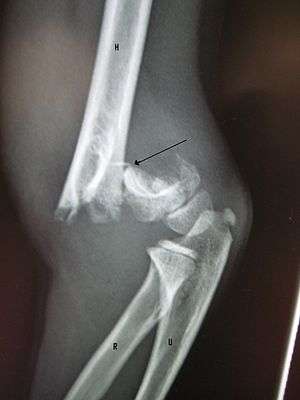

A displaced supracondylar fracture